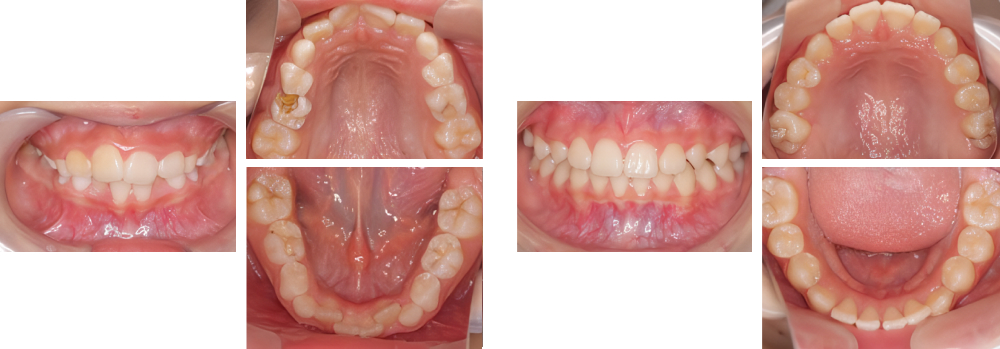

小児矯正

| 治療内容 | 叢生に対して床矯正を使用し治療を行った |

|---|---|

| 治療期間・回数 | 20カ月間・19回(動的治療まで) |

| 費用 ※自由診療となります |

矯正検査①:33,000円 床装置(ネジあり):77,000円 ×2 床装置(ネジなし):55,000円 ×2 |